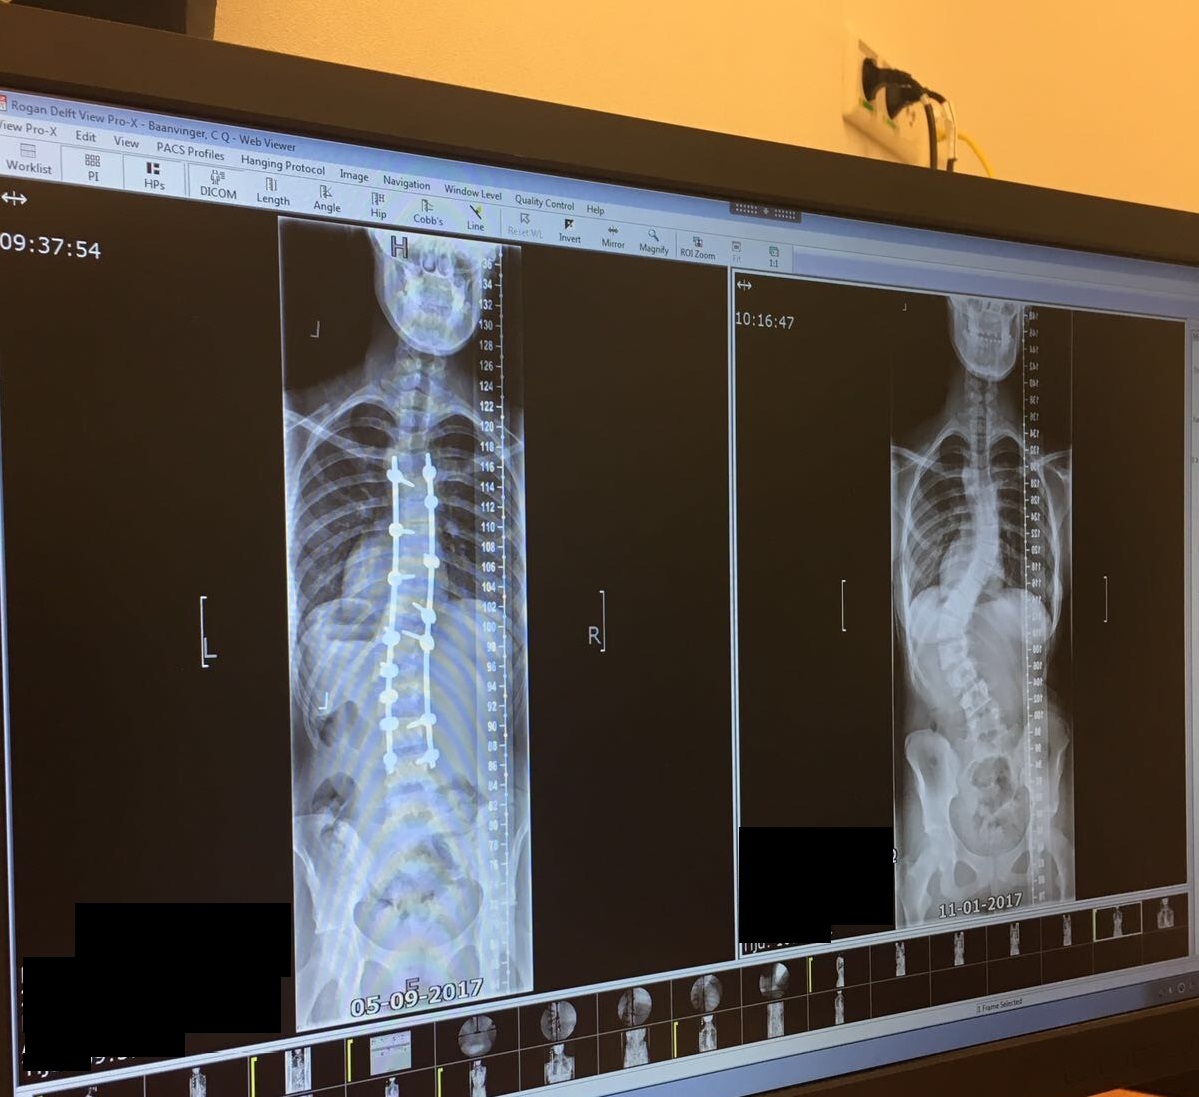

Een zonnige nazomermiddag. We bevinden ons in het restaurant van de Sint Maartenskliniek in Nijmegen. Cheyenne Baanvinger (16) heeft net even een balletje hooggehouden voor de bij dit artikel behorende fotoshoot. Aan niets was te merken dat zij iets meer dan een jaar geleden een zware scoliose-operatie heeft gehad, waarbij de bocht in haar wervelkolom van 66 graden werd gecorrigeerd tot 18 graden. ‘Ook voor mijn operatie had ik nergens last van’, vertelt ze, terwijl moeder Rina, opa Theo en oma Trudy aan tafel schuiven. ‘Mijn spieren zijn altijd heel soepel geweest, omdat ik zoveel sport. Maar ik stond blijkbaar heel erg scheef.’ ‘Iedereen zag ‘t: ze stond echt naast haar heupen’, voegt oma Trudy toe.

De kromming van Cheyennes ruggengraat werd steeds groter. En dus besloot de behandeld arts haar door te verwijzen naar de specialisten van de Sint Maartenskliniek. Daar bleek dat een operatie onvermijdelijk was. De ingreep was in juli 2017. In de aanloop van de operatie bleef Cheyenne gewoon doen wat ze altijd al deed. Rina: ‘Tot een week voor de operatie heeft ze nog getraind en wedstrijden gespeeld. En één dag voor de operatie deed ze nog mee aan bungee-voetbal… Dat kan je toch niet geloven!’

Na de operatie, uitgevoerd door dr. Horsting en dr. De Klerk, bleek ook Cheyenne kwetsbaar te zijn. Het revalidatieproces ging met ups & downs. En al die maanden moest MO17-1 van RKVV Roosendaal haar spits missen. ‘Cheyenne was boos’’, zegt oma Trudy. ‘Ze ging het ziekenhuis in toen ze nog alles kon. Ze kwam eruit en kon niets meer. Ze kreeg veel medicijnen en had veel pijn. En als we haar wilden helpen, dan mocht het niet van haar. Cheyenne was Cheyenne niet meer. We snapten het wel: ze wilde hier zo snel mogelijk klaar mee zijn. Weg uit dat bed, weg met die rolstoel. Maar dat ging niet 1-2-3. Toch heeft ze altijd weten door te zetten.’ ‘Mijn familie, mentor, vrienden en teamgenoten hebben me steeds enorm gesteund’, onderstreept Cheyenne. ‘Daar ben ik hen erg dankbaar voor.’ Na een aantal weken nam de pijn gelukkig af. Cheyenne hoefde minder medicatie te gebruiken. En na vijf weken kon ze al een heleboel dingen zelf doen, zoals douchen en aankleden. Zij keek erg uit naar de afspraken met de orthopeed, want dat betekende voor haar dat ze weer een stapje vooruit was gegaan en beetje bij beetje haar dingetjes weer mocht oppakken.